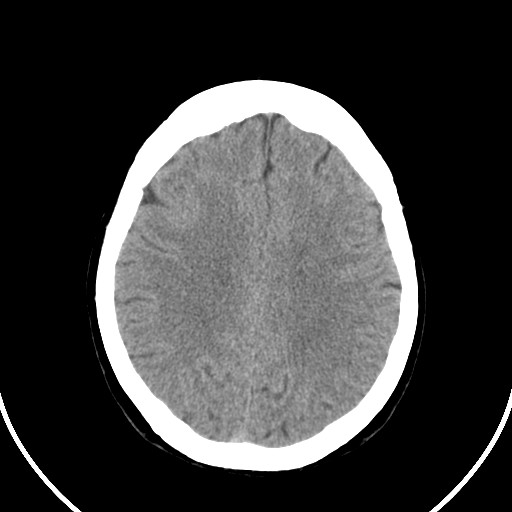

标题: CT21850:女,56岁,右中指淤肿,右手麻痹1天

女,56岁,右中指淤肿,右手麻痹1天

右侧侧脑室旁脑白质腔隙性脑梗死。

右侧基底节多发小梗塞

作者: huangyinshan    时间: 2009-8-25 15:37

右基底结区腔梗

右侧基底节区腔隙性脑梗塞

右侧基底节多发腔梗!

双侧侧脑室额角旁对称性略低密度影,边缘模糊,无占位效应,考虑轻度脑白质稀疏症(病人有高血压吗).,右枕叶低密度影多为伪影,不放心薄扫一下.

考虑脑白质病。

考虑脑白质病

右枕叶条状低密度影不应该忽略可能极具意义